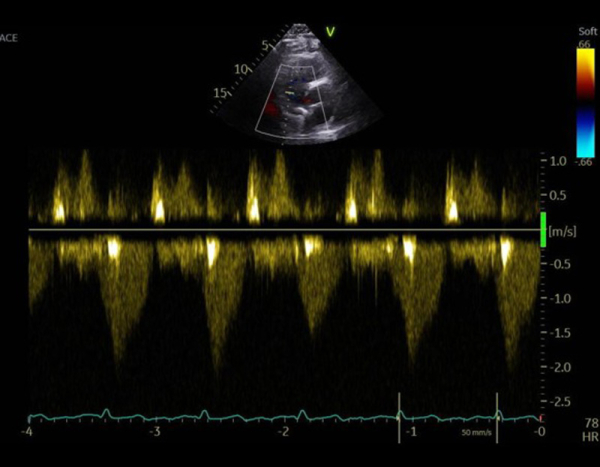

Vidéo 3

FEVG 30% , hypokinésie diffuse, pas de valvuloptahie aortique ni mitrale. VD non dilaté, normokinétique avec IT modérée. Prothèse en place avec passage de bulles résiduelles modéré. Sonde de DAI semblant extrêmement mobile.